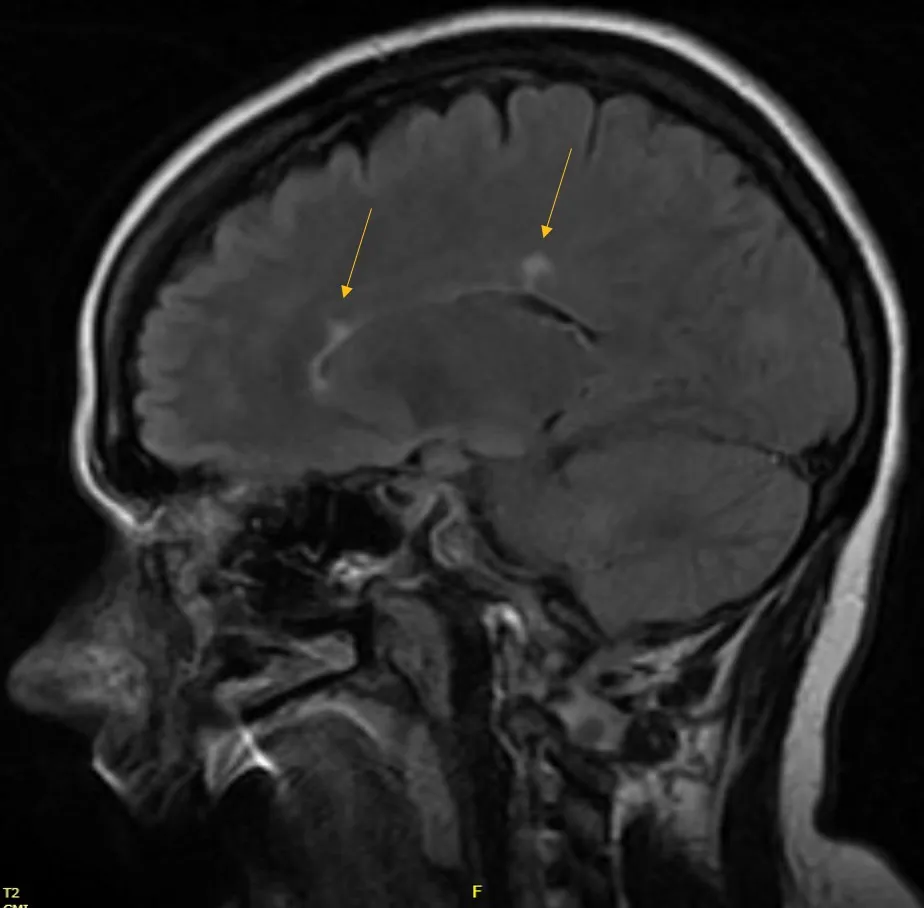

2019 Brain MRI

A young female presented to clinic for assessment. She first had symptoms of numbness that lasted over several months. After undergoing MRI of the brain in 2019, she was not given a diagnosis.